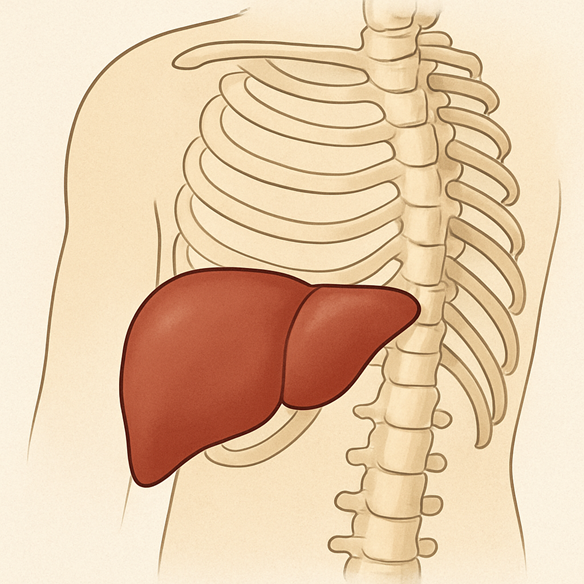

• Fígado

Terapia manual na região do fígado

Por exemplo, ao trabalhar manualmente a região do fígado, conseguimos melhorar a mobilidade do:

- Abdômen

- Tórax

- Costelas

Com isso, eliminamos restrições que estavam “prendendo” os movimentos naturais do corpo.